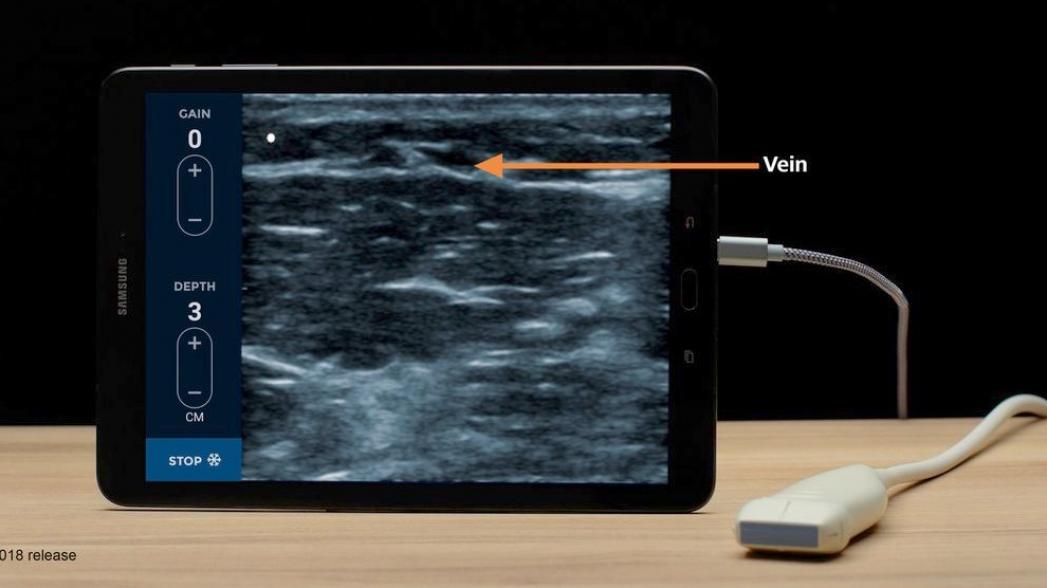

Это устройство, получившее название EchoNous Vein, может использоваться при оказании помощи различным пациентам, включая взрослых и детей.

Этот портативный прибор позволяет быстро получить четкое изображение на глубине от 1 до 5 см для визуализации поверхностных и глубокорасположенных вен. При этом управление осуществляется двумя кнопками на ручке прибора.

При работе устройство использует интеллектуальное программное обеспечение компании Uscan на базе искусственного интеллекта. По словам представителей компании, применение технологии искусственного интернета и миниатюризация ультразвукового устройства позволяет предложить медицинскому персоналу средство, существенно упрощающую их работу.